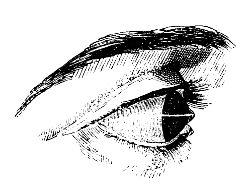

| Diseases of the Eye and its Appendages | 245 |

| Diseases of the Eyeball | 257 |

| Strabismus | 292 |